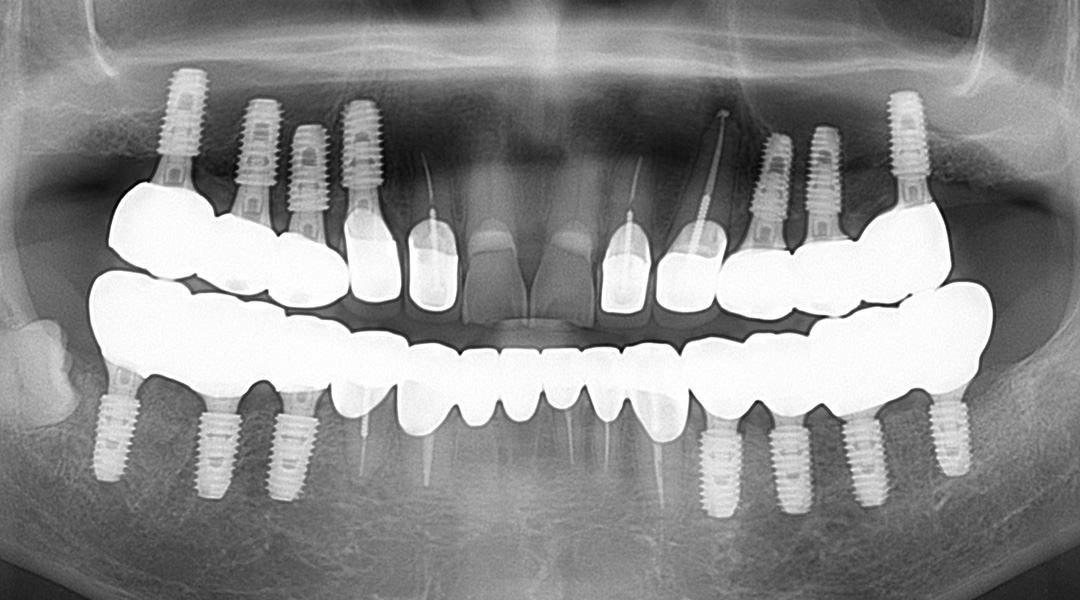

BEFORE & AFTER

갤러리치과의원의 전후 사진을 확인해보세요.

- 무통임플란트